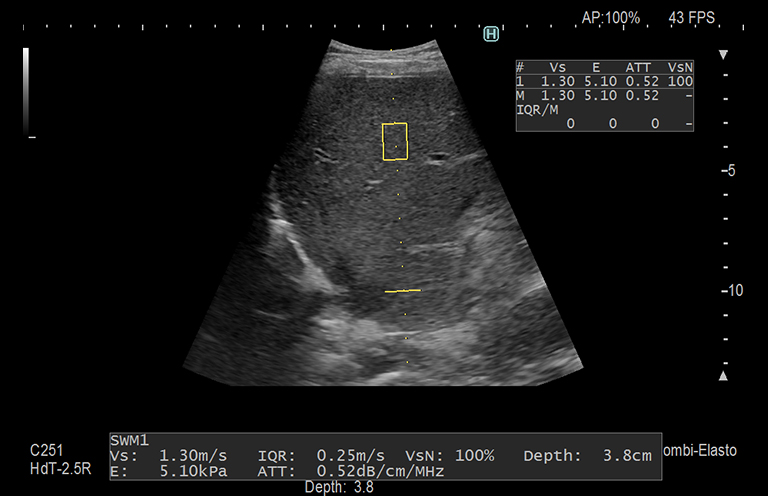

Aplicación: Abdomen

Función/análisis: SWM/ATT

Comentarios: Hígado